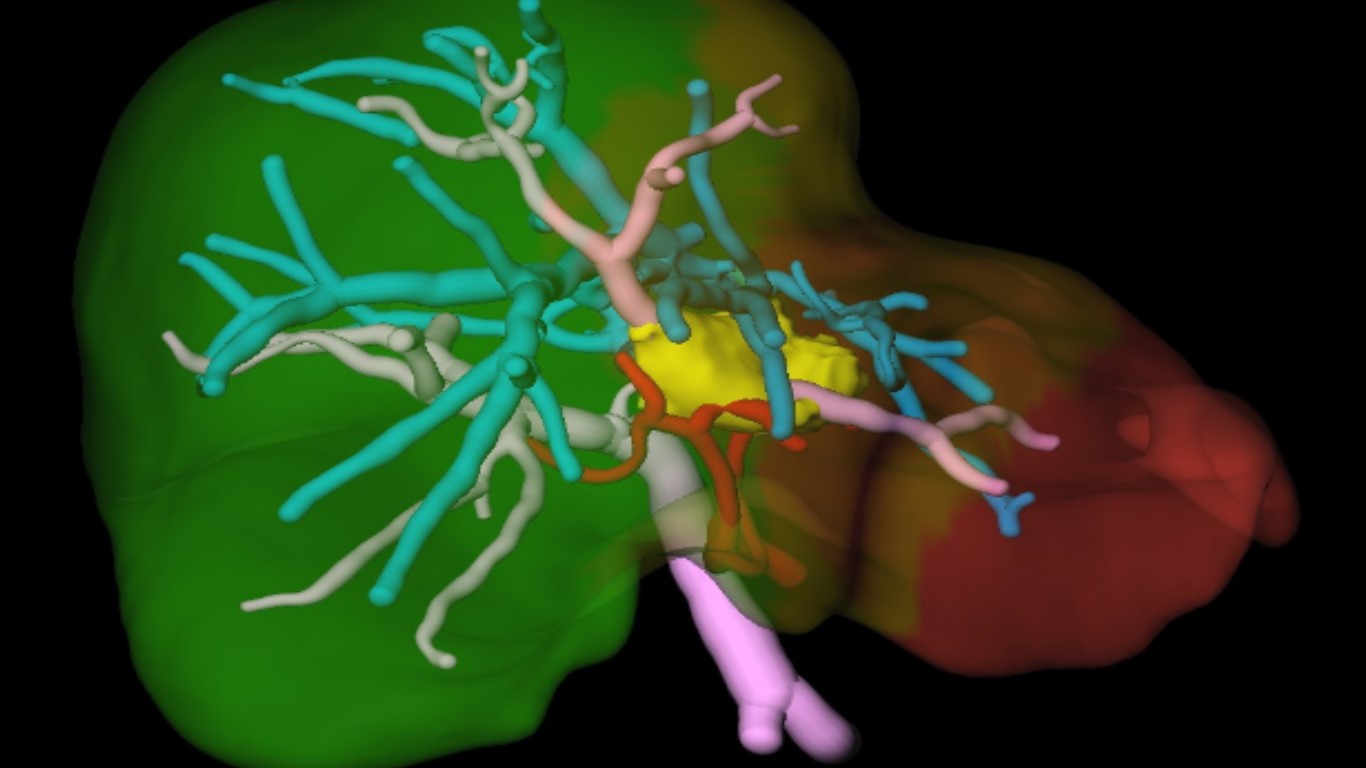

Рентгенологами была создана 3D-компьютерная модель печени, что позволило врачам видеть расположение и размеры опухоли, ее внедрение в важные сосудистые структуры.